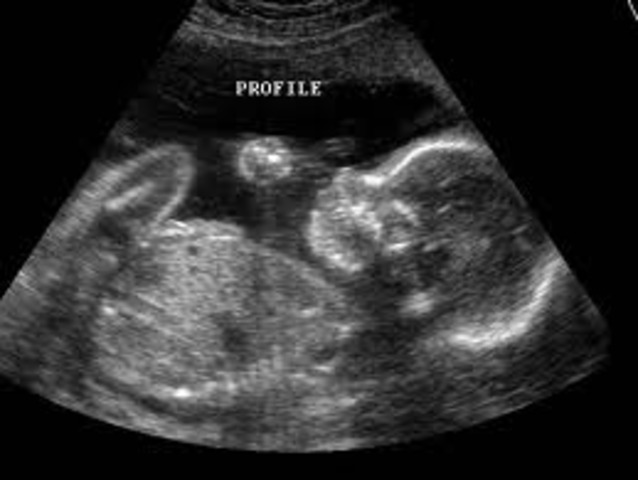

• Month 8- Baby

Month 8- Baby

Size is about 14-16 in. long and 2 1/2-3 lbs. Weight gain continues rapidly. May react to loud noises with a reflex jerking action. moves into a head-dwon position